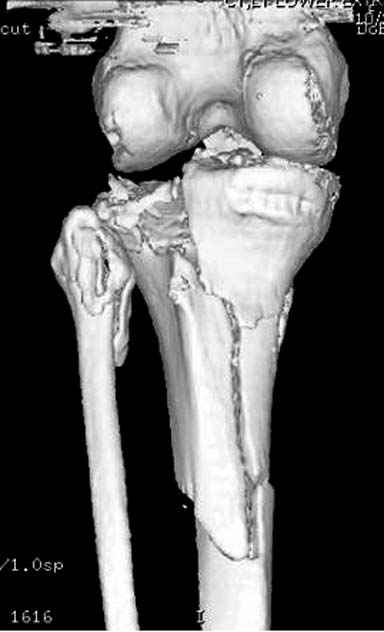

Отдельные переломы тибиал плато и перелом проксимальной трети большеберцовой кости отличаются от переломов тибиал плато с вовлечением диафиза. Здесь перелом тибиал плато типа Schatzker VI, полученный в результате высокоэнергетической травмы. Перелом метафиза образовал отрыв суставной поверхности от диафиза с вовлечением медиального и латерального мыщелков. Двухмыщелковые переломы из-за укрочения опасны развитием компартаментального синдрома, повреждением латерального мениска и связок.

На вашем место я бы подождал с фиксацией до готовности кожных покровов, и за это время можно было подобрать соответствующий фиксатор, т.е более длинная пластина снаружи и медиальная пластина на апексе перелома как подпорка. Здесь приемлем как раз минимальный доступ.

Здесь пару случаев для сравнения,...в первых 1-4 слайдах метод фиксации одним фиксатором, как видно после 8 месяцев сохранилась ось. С 5 по 9 вариант двумя пластинами...